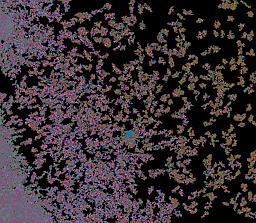

Pancreatic ductal adenocarcinoma is a lethal disease with limited treatment options and poor survival. We studied 83 spatial samples from 31 patients (11 treatment-naïve and 20 treated) using single-cell/nucleus RNA sequencing, bulk-proteogenomics, spatial transcriptomics and cellular imaging. Subpopulations of tumor cells exhibited signatures of proliferation, KRAS signaling, cell stress and epithelial-to-mesenchymal transition. Mapping mutations and copy number events distinguished tumor populations from normal and transitional cells, including acinar-to-ductal metaplasia and pancreatic intraepithelial neoplasia. Pathology-assisted deconvolution of spatial transcriptomic data identified tumor and transitional subpopulations with distinct histological features. We showed coordinated expression of TIGIT in exhausted and regulatory T cells and Nectin in tumor cells. Chemo-resistant samples contain a threefold enrichment of inflammatory cancer-associated fibroblasts that upregulate metallothioneins. Our study reveals a deeper understanding of the intricate substructure of pancreatic ductal adenocarcinoma tumors that could help improve therapy for patients with this disease.